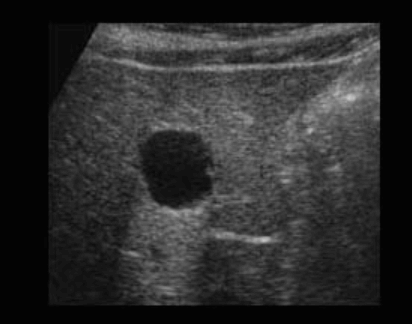

US finding

- 무에코(anechoic)

- 경계가 분명하다(sharp margin)

- 후방음향증강(posterior enhancement)

- 측방음영(lateral shadow)

simple cyst ② polycystic liver disease (PLD)